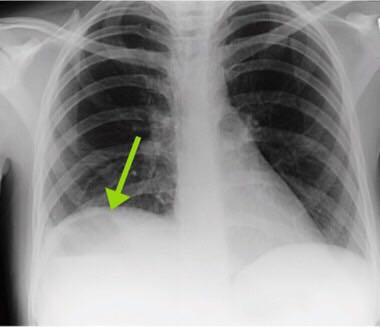

患者女,26岁,因急性腹痛、呕吐、发热一周入院。一周前患者曾因顺产失败行紧急剖宫产术。查体:发热,心率快,全腹不适。WBC及CRP、血沉均升高。超声如图,可见液体。X线可见气液平。进一步行CT检查确认结果如图。这个是怎么回事?